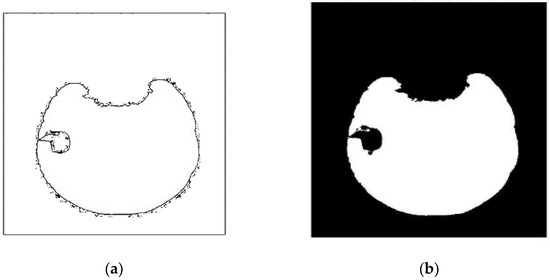

3.1. Dataset and Pre-Processing

3.3. Data Processing and Contourlet Transform